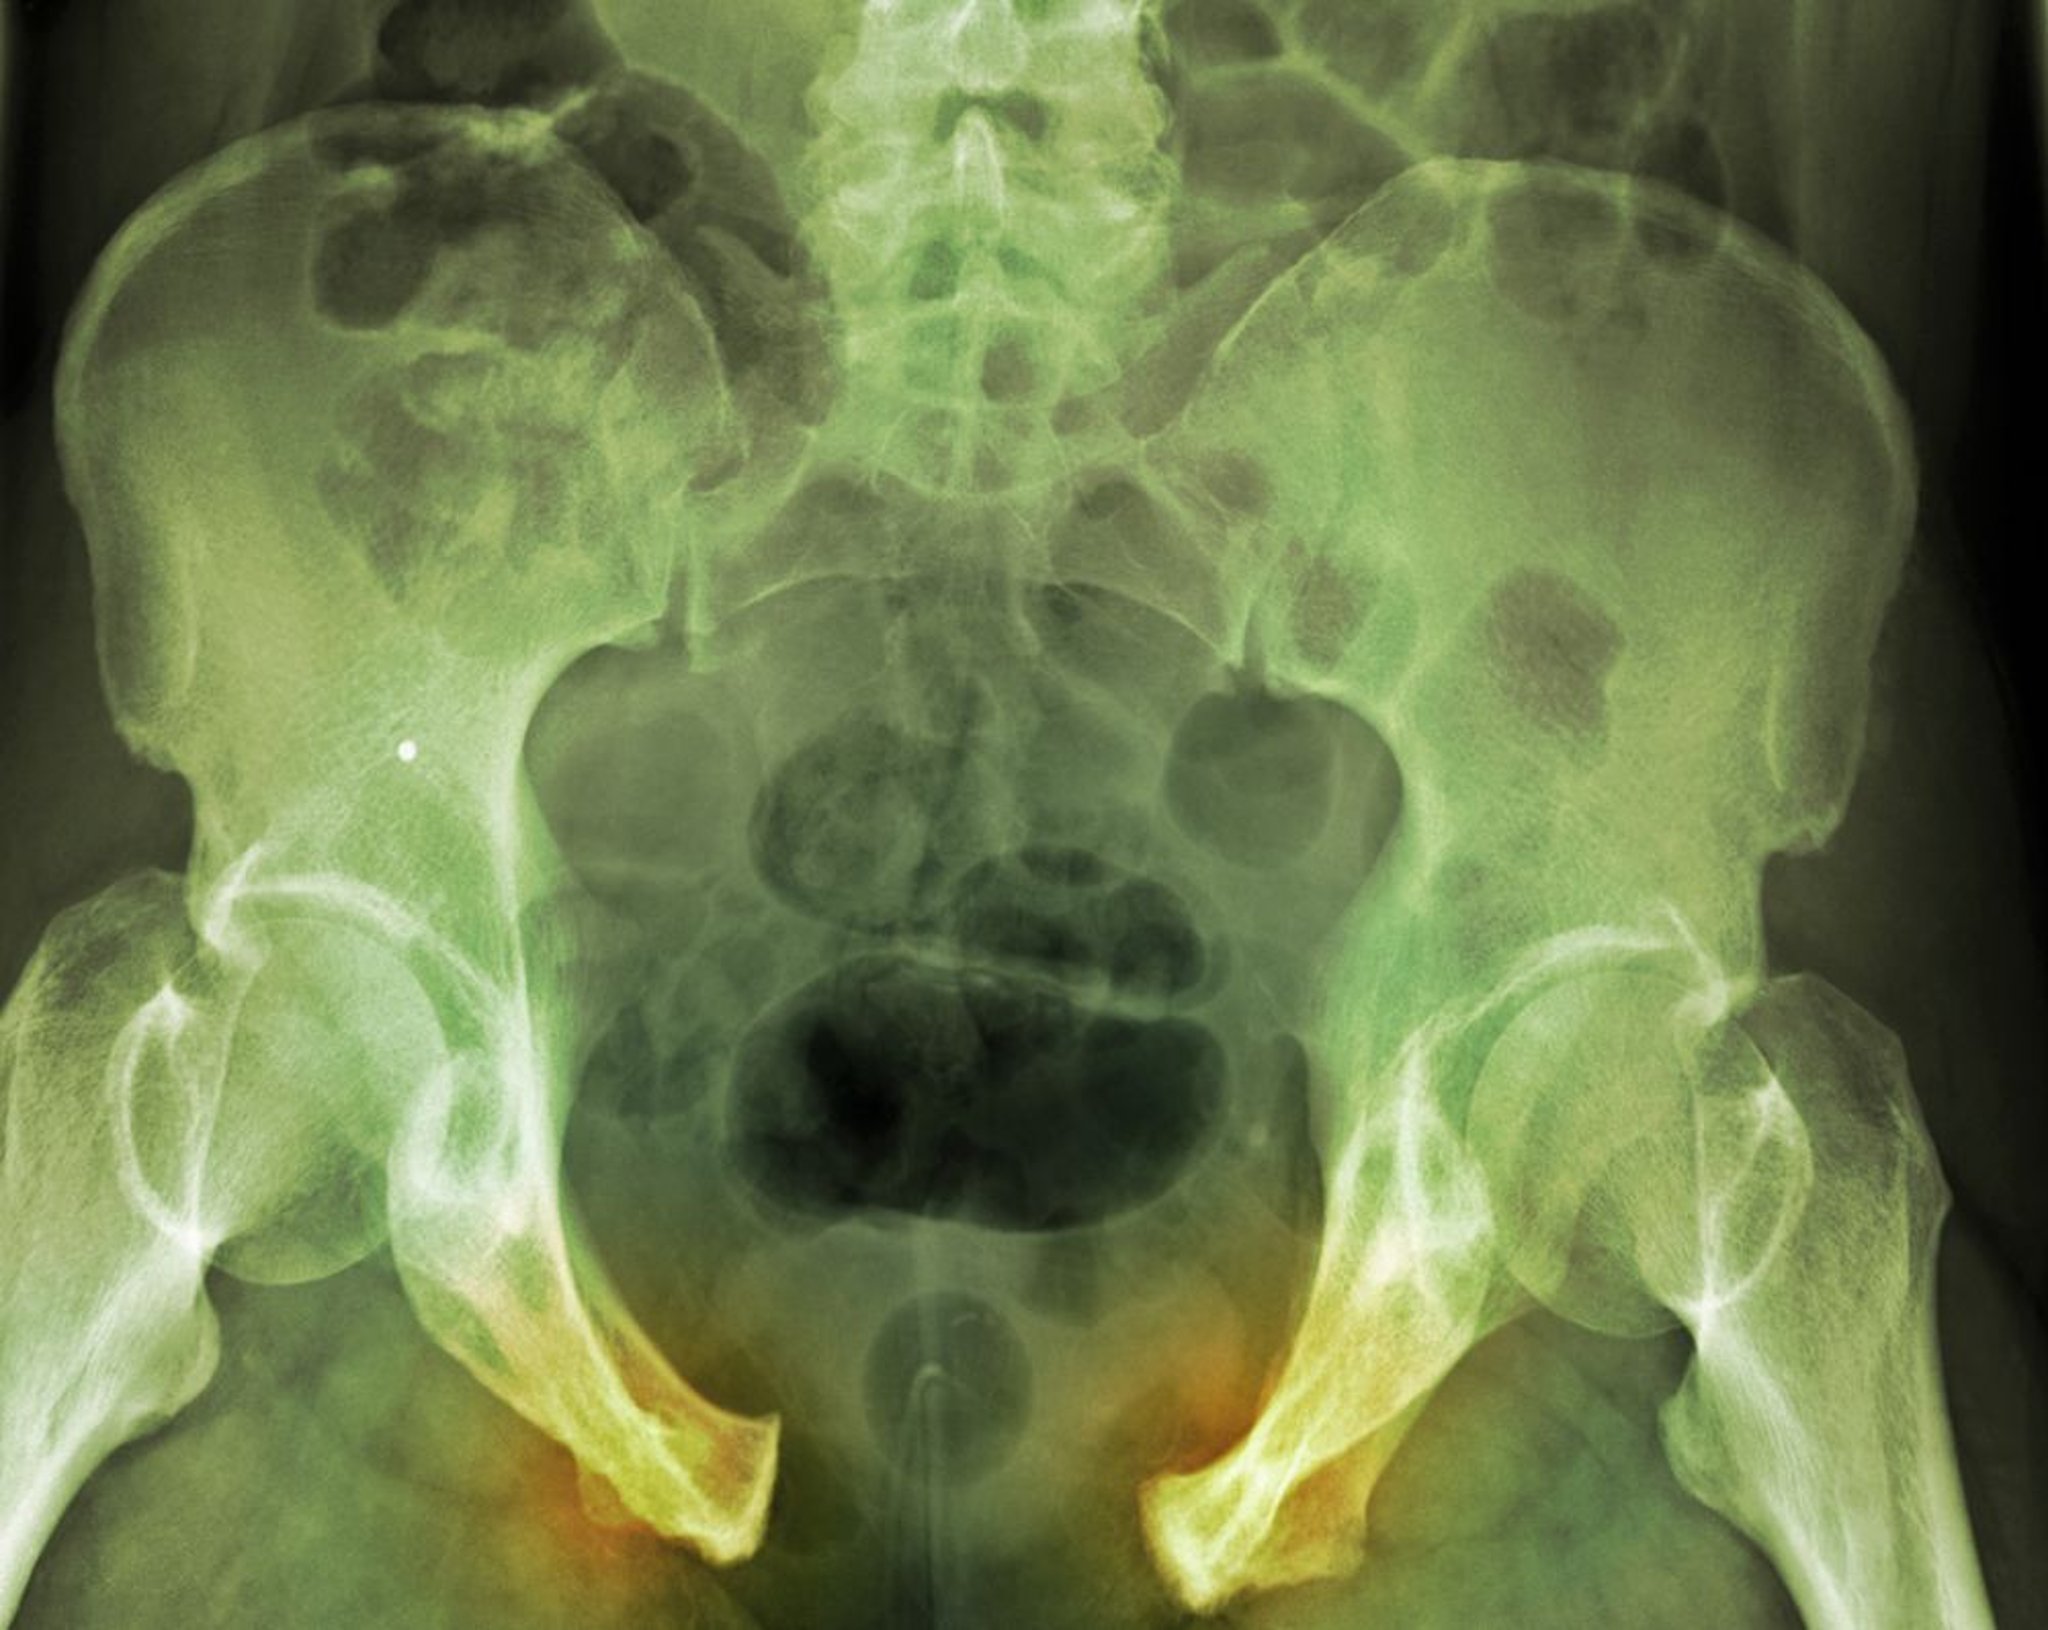

Las fracturas pélvicas pueden implicar la sínfisis púbica, huesos ilíacos, acetábulo, articulación sacroilíaca o sacro. Éstas van desde lesiones estables mínimamente desplazadas causadas por caídas con baja energía a fracturas desplazadas drásticamente y lesiones inestables que pueden causar hemorragia masiva. Pueden asociarse con lesiones genitourinarias, intestinales, y neurológicas. El diagnóstico se realiza mediante radiografías y generalmente tomografía computarizada. Las fracturas estable leves sólo requieren tratamiento sintomático. Las fracturas inestables y las fracturas con hemorragia significativa por lo general requieren fijación externa o la reducción abierta con fijación interna.

Las fracturas pélvicas se deben considerar si los pacientes tienen dolor en la región pélvica o la cadera o han tenido un trauma mayor. Una radiografía de pelvis anteroposterior muestra la mayoría de las fracturas.

Una fractura desplazada indica que el anillo pélvico está seccionado, lo que sugiere otra fractura o interrupción sindesmótica o ligamentosa. Pueden ser necesarias vistas radiográficas especializadas (p. ej., vistas de Judet para el acetábulo).